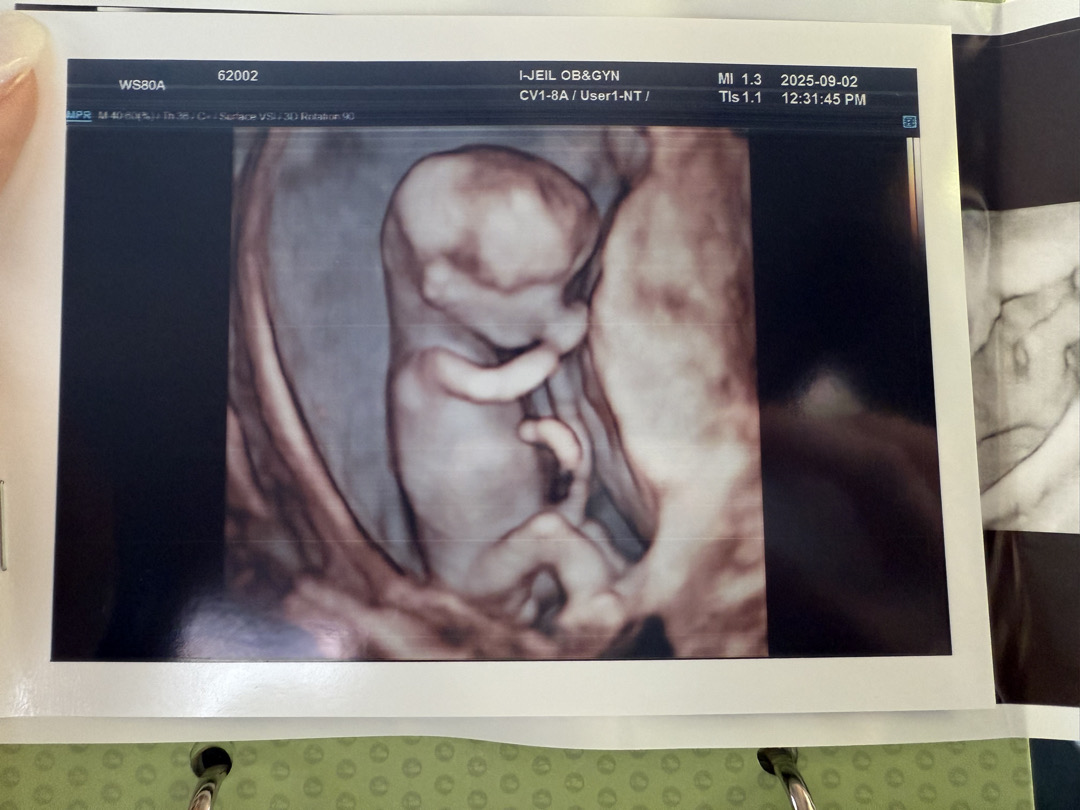

12주차 각도법 잘 아시는분들 알려주시면 정말 감사합니다~~

저 갈라진부분이 아들인지 딸인지 잘 모르겠는데 혹시 잘 보시는분들 계실까요??

밑에 사진더 첨부해여~~~